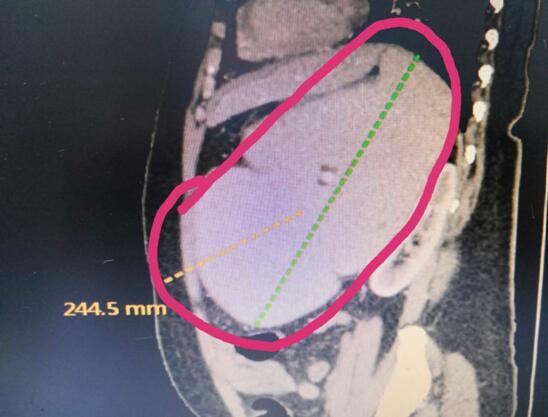

病例B

患者B,女,51歲,因牙齦出血1年入院,入院診斷為:乙肝,肝炎后肝硬化,門脈高壓癥,巨脾,脾亢,白細(xì)胞、血小板減少,中度貧血。5年前,曾在外院行介入脾栓塞術(shù),脾臟不僅沒有縮小,反而越來越大,脾下緣已經(jīng)超過腹部正中線、抵達(dá)臍部,就像幾個(gè)月“身孕”的婦女,給病人帶來巨大身心負(fù)擔(dān)。

(術(shù)前腹部CT顯示巨脾)

2020年2月28日,手術(shù)團(tuán)隊(duì)在3D腹腔鏡下為患者行巨脾切除術(shù)。因?yàn)椴∪嗽薪槿肫⑴K栓塞術(shù),手術(shù)遠(yuǎn)比想象中困難,巨脾與左側(cè)肝臟、膈頂、左側(cè)腹膜、結(jié)腸脾曲均有致密粘連,改變平時(shí)手術(shù)順序,先結(jié)扎脾動脈,離斷脾蒂,最后再分離脾周韌帶及粘連。完整切除巨脾后,分成小塊從小孔取出。